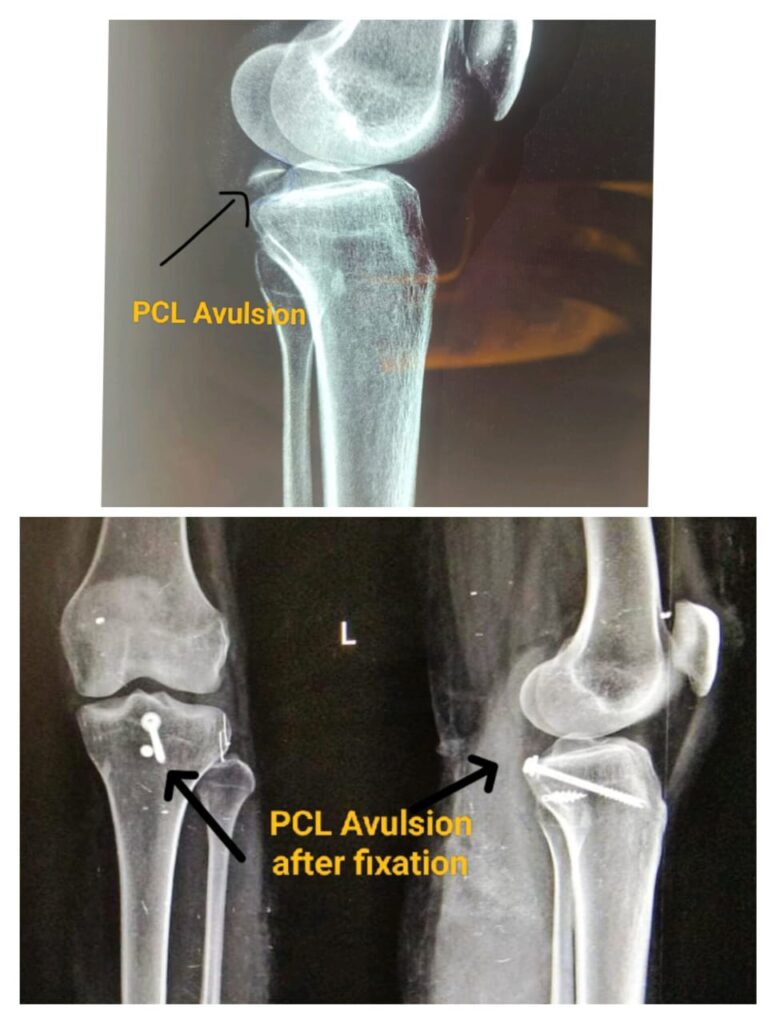

Advantages of Arthroscopy

Early mobilisation

Less stiffness of joint

Less chances of infection

Open fixation of tibial spine fractures carries a risk of knee stiffness, infection & metallic implant in knee joint